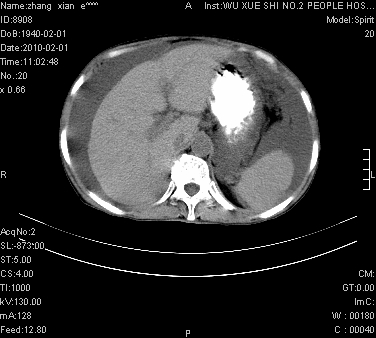

标题: CT24434:70岁 女 腹胀,腹水原因待查 [打印本页]

大量腹水,脾脏囊性占位,子宫颈占位,右侧腹股沟淋巴结肿大,建议+c,先查妇科。

大量腹水,脾囊肿可能性大,建议增强

腹盆腔大量积液,子宫增大,子宫颈增大外形不规则,内见低密度影,膀胱后壁显示不清,右腹股沟肿大淋巴结,脾脏囊性占位,子宫颈占位,子宫颈癌?建议增强。

大量腹水,右肾、脾囊肿可能性大          考虑左侧附件区占位,建议增强